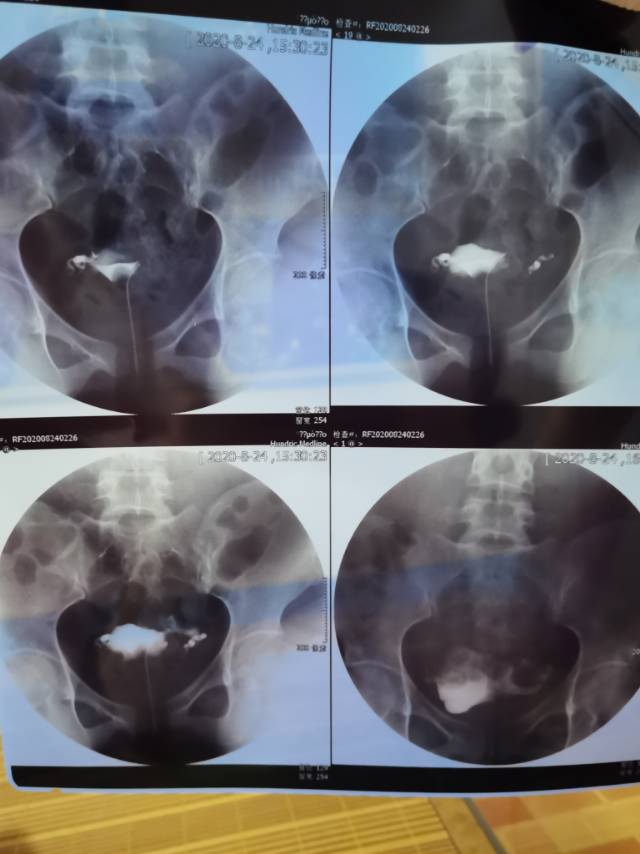

做完输卵管造影第六天了小腹还是感觉沉甸甸的如

可以热敷腹部,如果有发热,腹痛加剧,白带量多,有异味,随时就医